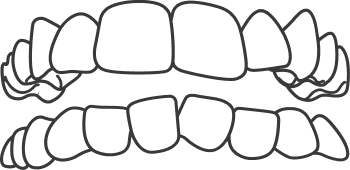

An open bite is where the front teeth do not overlap the lower teeth. This is caused by oral habits like finger sucking, tongue thrusting, or when the jaws don't grow evenly.

When one or more upper teeth bite on the inside of the lower teeth, this condition is called a crossbite. This can happen on either one or both sides of the jaw and affect front or back teeth.

Normally, there should be overlap of 2 mm but when the upper front teeth overlap the lower front teeth for more than 2mm such that they do not touch at all; an overbite is seen.

This occurs when there are gaps between the teeth and is the opposite of crowding. This can occur between two or more teeth and can be caused due to missing teeth, smaller teeth or oral habits like tongue thrusting, thumb sucking.

When teeth that are crooked and overlap mainly due to lack of space, this condition is called Crowding. Some of the causes include improper eruption of teeth, early or late loss of milk teeth or when teeth are larger than the space available in the jaw.

An underbite occurs when the lower teeth protrude past the front teeth, preventing normal function of your front teeth or molars.